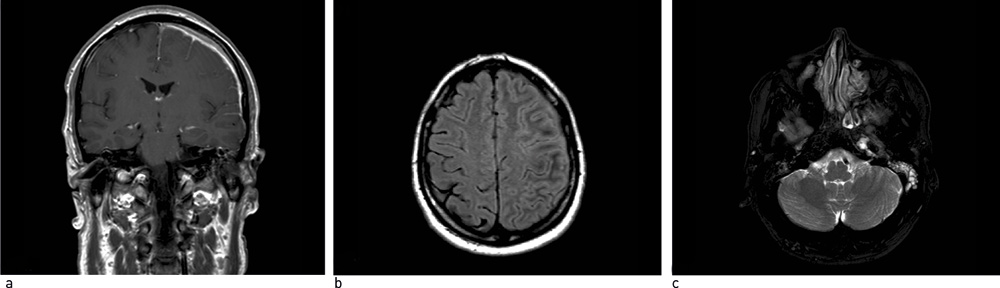

Pasienten gjennomgikk en omfattende utredning. Man fikk avkreftet differensialdiagnostiske muligheter som er nevnt i litteraturen (fig 3), med unntak av Wegeners granulomatose som ikke sikkert kunne utelukkes. Den videre utredningen ble derfor rettet mot dette. Det eneste positive funnet var c-ANCA, som var svakt positiv initialt, men senere innenfor referanseområdet. Blodprøver for øvrig var normale. Det ble ikke funnet hudforandringer, hjerte- eller nyreaffeksjon. CT av tinningbein viste væske og bløtdelsfortykkelse i mellomøret og fortettede mastoidalceller på venstre side. Ved CT av bihuler så man hypoplastisk venstre maksillærsinus med slimhinnefortykkelse og væskespeil, men ingen granulomer. Biopsi av respiratorisk slimhinne konkluderte med uspesifikk kronisk betennelse, og ingen vaskulitt eller granulomer. CT thorax viste mulig progresjon av én av de små uspesifikke nodulære fortetningene som ble påvist i venstre overlapp ved sykdomsdebut, men forandringen var ikke tilgjengelig for biopsi (fig 4).